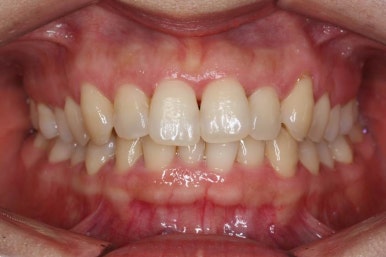

마찬가지로 부산설측교정 키다리아저씨치과에서 처음 내원하셨을 당시의 입안 모습입니다.

어금니쪽은 특별히 이상이 없었고, 위아래 앞니만 삐뚤한 상태였습니다.

전후사진을 비교해 보겠습니다.

삐뚤었던 부위들은 가지런하게 정리가 되었습니다.